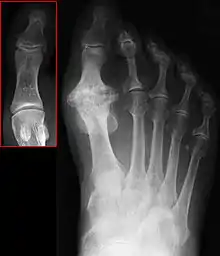

Hallux rigidus or stiff big toe is degenerative arthritis and stiffness due to bone spurs that affects the metatarsophalangeal joints (MTP) at the base of the hallux (big toe).

| Hallux not labeled but visible at upper left. | |